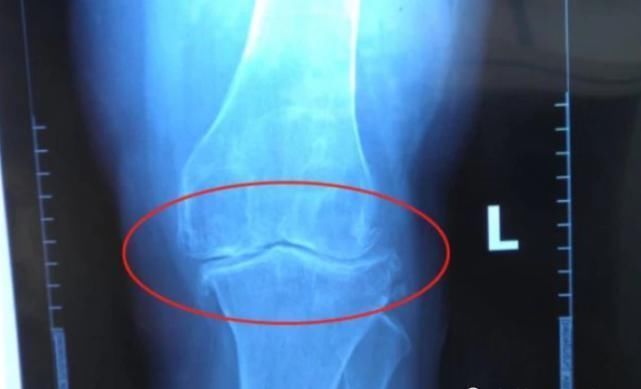

如何判断自己是否还有长高的潜力骨骺线没有闭合,就说明骨骼还有生长发育的空间,这就是你还有长高的希望。这也是为什么有些人,明明没有到18岁,身高却依旧不长的原因,可能就是由于某方面的原因,导致骨骺线提前闭合了,可以去医院拍片,让医生看一下,自己的骨骺线是否闭合。